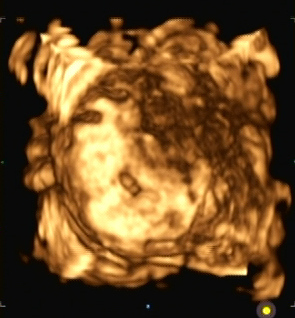

Ein zunächst durchgeführtes CTG war unauffällig. Im Rahmen der sonografischen Untersuchung zeigte sich der Fötus soweit beurteilbar zeitgerecht entwickelt. Dennoch konnte ein Anhydramnion festgestellt werden(Abb. 1, 2), weshalb auch kein fetales Gesicht darstellbar war (Abb. 3).